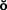

Unfortunately, periodontal disease often occurs after placement of fixed prostheses,26 especially where the cavosurface margin has been placed subgingivally27-29 or the prosthesis is overcontoured.30 Inflammation is more severe with poorly fitting restorations31 (Fig. 32-12), but even “perfect” margins have been associated with periodontitis.32 At recall appointments, particular attention is given to sulcular hemorrhage, furcation involvement, and calculus formation as early signs of periodontal disease. Improperly contoured restorations should be recontoured or replaced.

Fig. 32-12 Periodontal failure resulting from defective fixed prostheses. A, Inadequate margins and contour. B, Appearance before surgery. C, Flap reflected. D, Appearance after surgical recontouring. E, Radiograph of new cast restorations. F, Replacement restorations.

(Courtesy of Dr. C. L. Politis.)